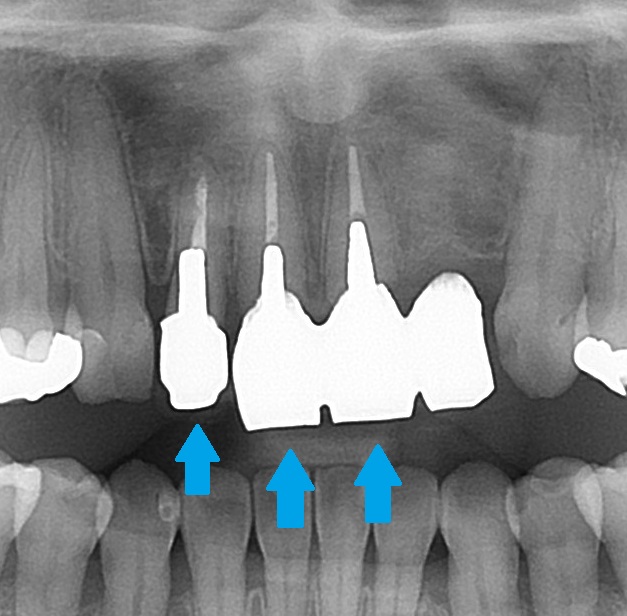

エックス線検査(レントゲン)で歯の中の状態を見てみると、

このような状態でした。

こちらの歯、3本が差し歯になっており、

後でお話しますが、メタルコアが入っています。

こちらの1本は歯が無く、ダミーの歯で繋がれています。昔に事故で抜いてしまったようです。

CT検査では、根の先に炎症などのトラブルはありませんでした。